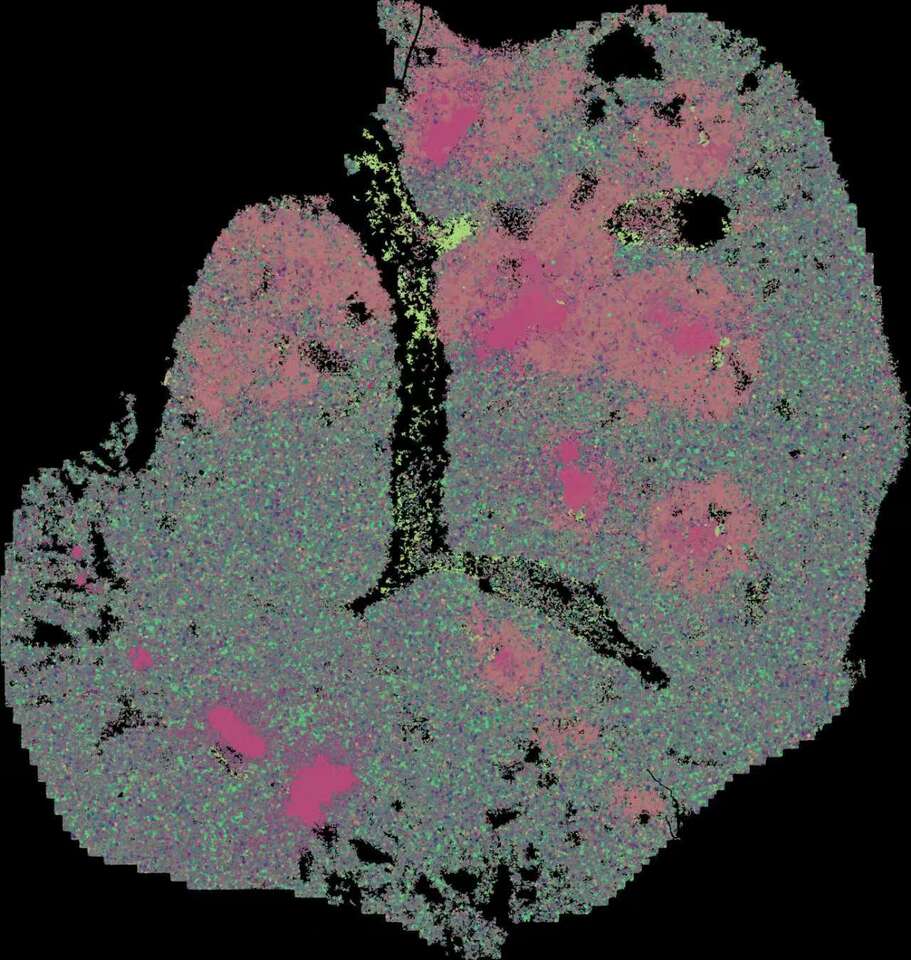

Schematic diagram

DC-T immunity hubs were physiologically detected in hamster lungs, which were mainly composed of spatially co-localized Cd160+Cd8+ T cells, Tnfrsf4+Cd4+ T cells and Ccr7+Ido1+ DCs. After SARS-CoV-2 infection, the immunity hubs expanded by recruiting Slamf9+ macrophages and Isg12+Cst7+ neutrophils to jointly clear viral infection. After viral clearance, the immunity hubs restored to physiological levels, and Slamf9+ macrophages may differentiate into Fbp1+ and Trem2+ macrophages, promoting inflammation resolution.